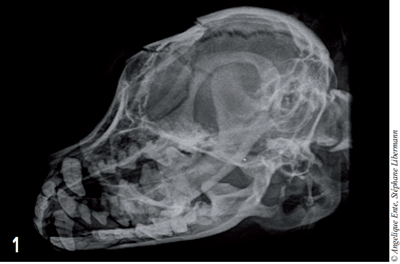

On effectue ensuite des radiographies de face et de profil du crâne (figures 1 et 2) : ces dernières montrent une fracture de l’os frontal induisant une embarrure.

D’autres traits de fractures sont visibles latéralement et caudalement (jusqu’à l’occiput).

Figure 1 – Radiographie du crâne en décubitus latéral. Une fracture de l’os frontal induit une embarrure.